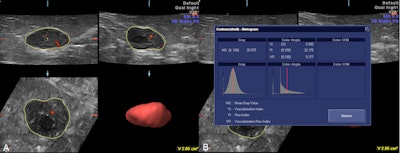

A 36-year-old woman with fibroadenoma. Decreased vascularization was seen in 3D power Doppler ultrasound (A) and also decreased vascular indexes in the histogram (B). Image courtesy of Dr. Ali Kupeli.

Three vascular indexes were obtained in this study using a Voluson 730 Expert, GE Healthcare system: vascularization index, flow index, and vascularization flow index. Vascularization index is the ratio of color voxels to all voxels in the interested volume and shows the density of vessels. Flow index is the mean value of all color voxels in the studied volume and represents average color intensity. Vascularization flow index is the combination of the two and the sum of weighted color voxels divided by all voxels, and it shows vascularization and perfusion.